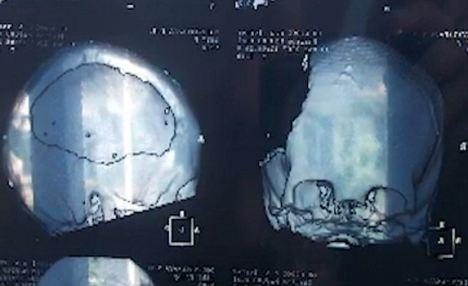

영국 일간지 데일리메일의 22일자 보도에 따르면, 러시아 상트페테르부르크에 사는 타이샤 시도로바(21)는 3년 전 교통사고로 두개골이 부서지고 뇌의 반쪽을 잃었다.

당시 의료진은 논리와 분석 등을 담당하는 뇌의 일부분을 잘라내고 특수장비 등을 동원해 조각난 두개골을 고정시켰다.